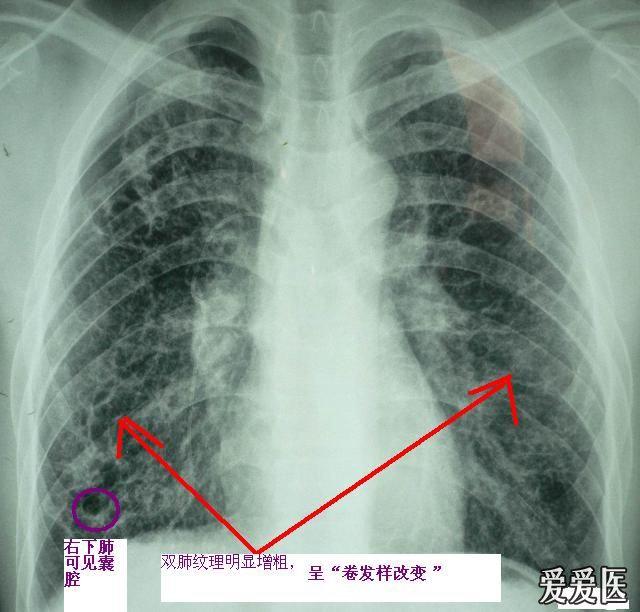

几组肺炎ct读片大畅带你来看图